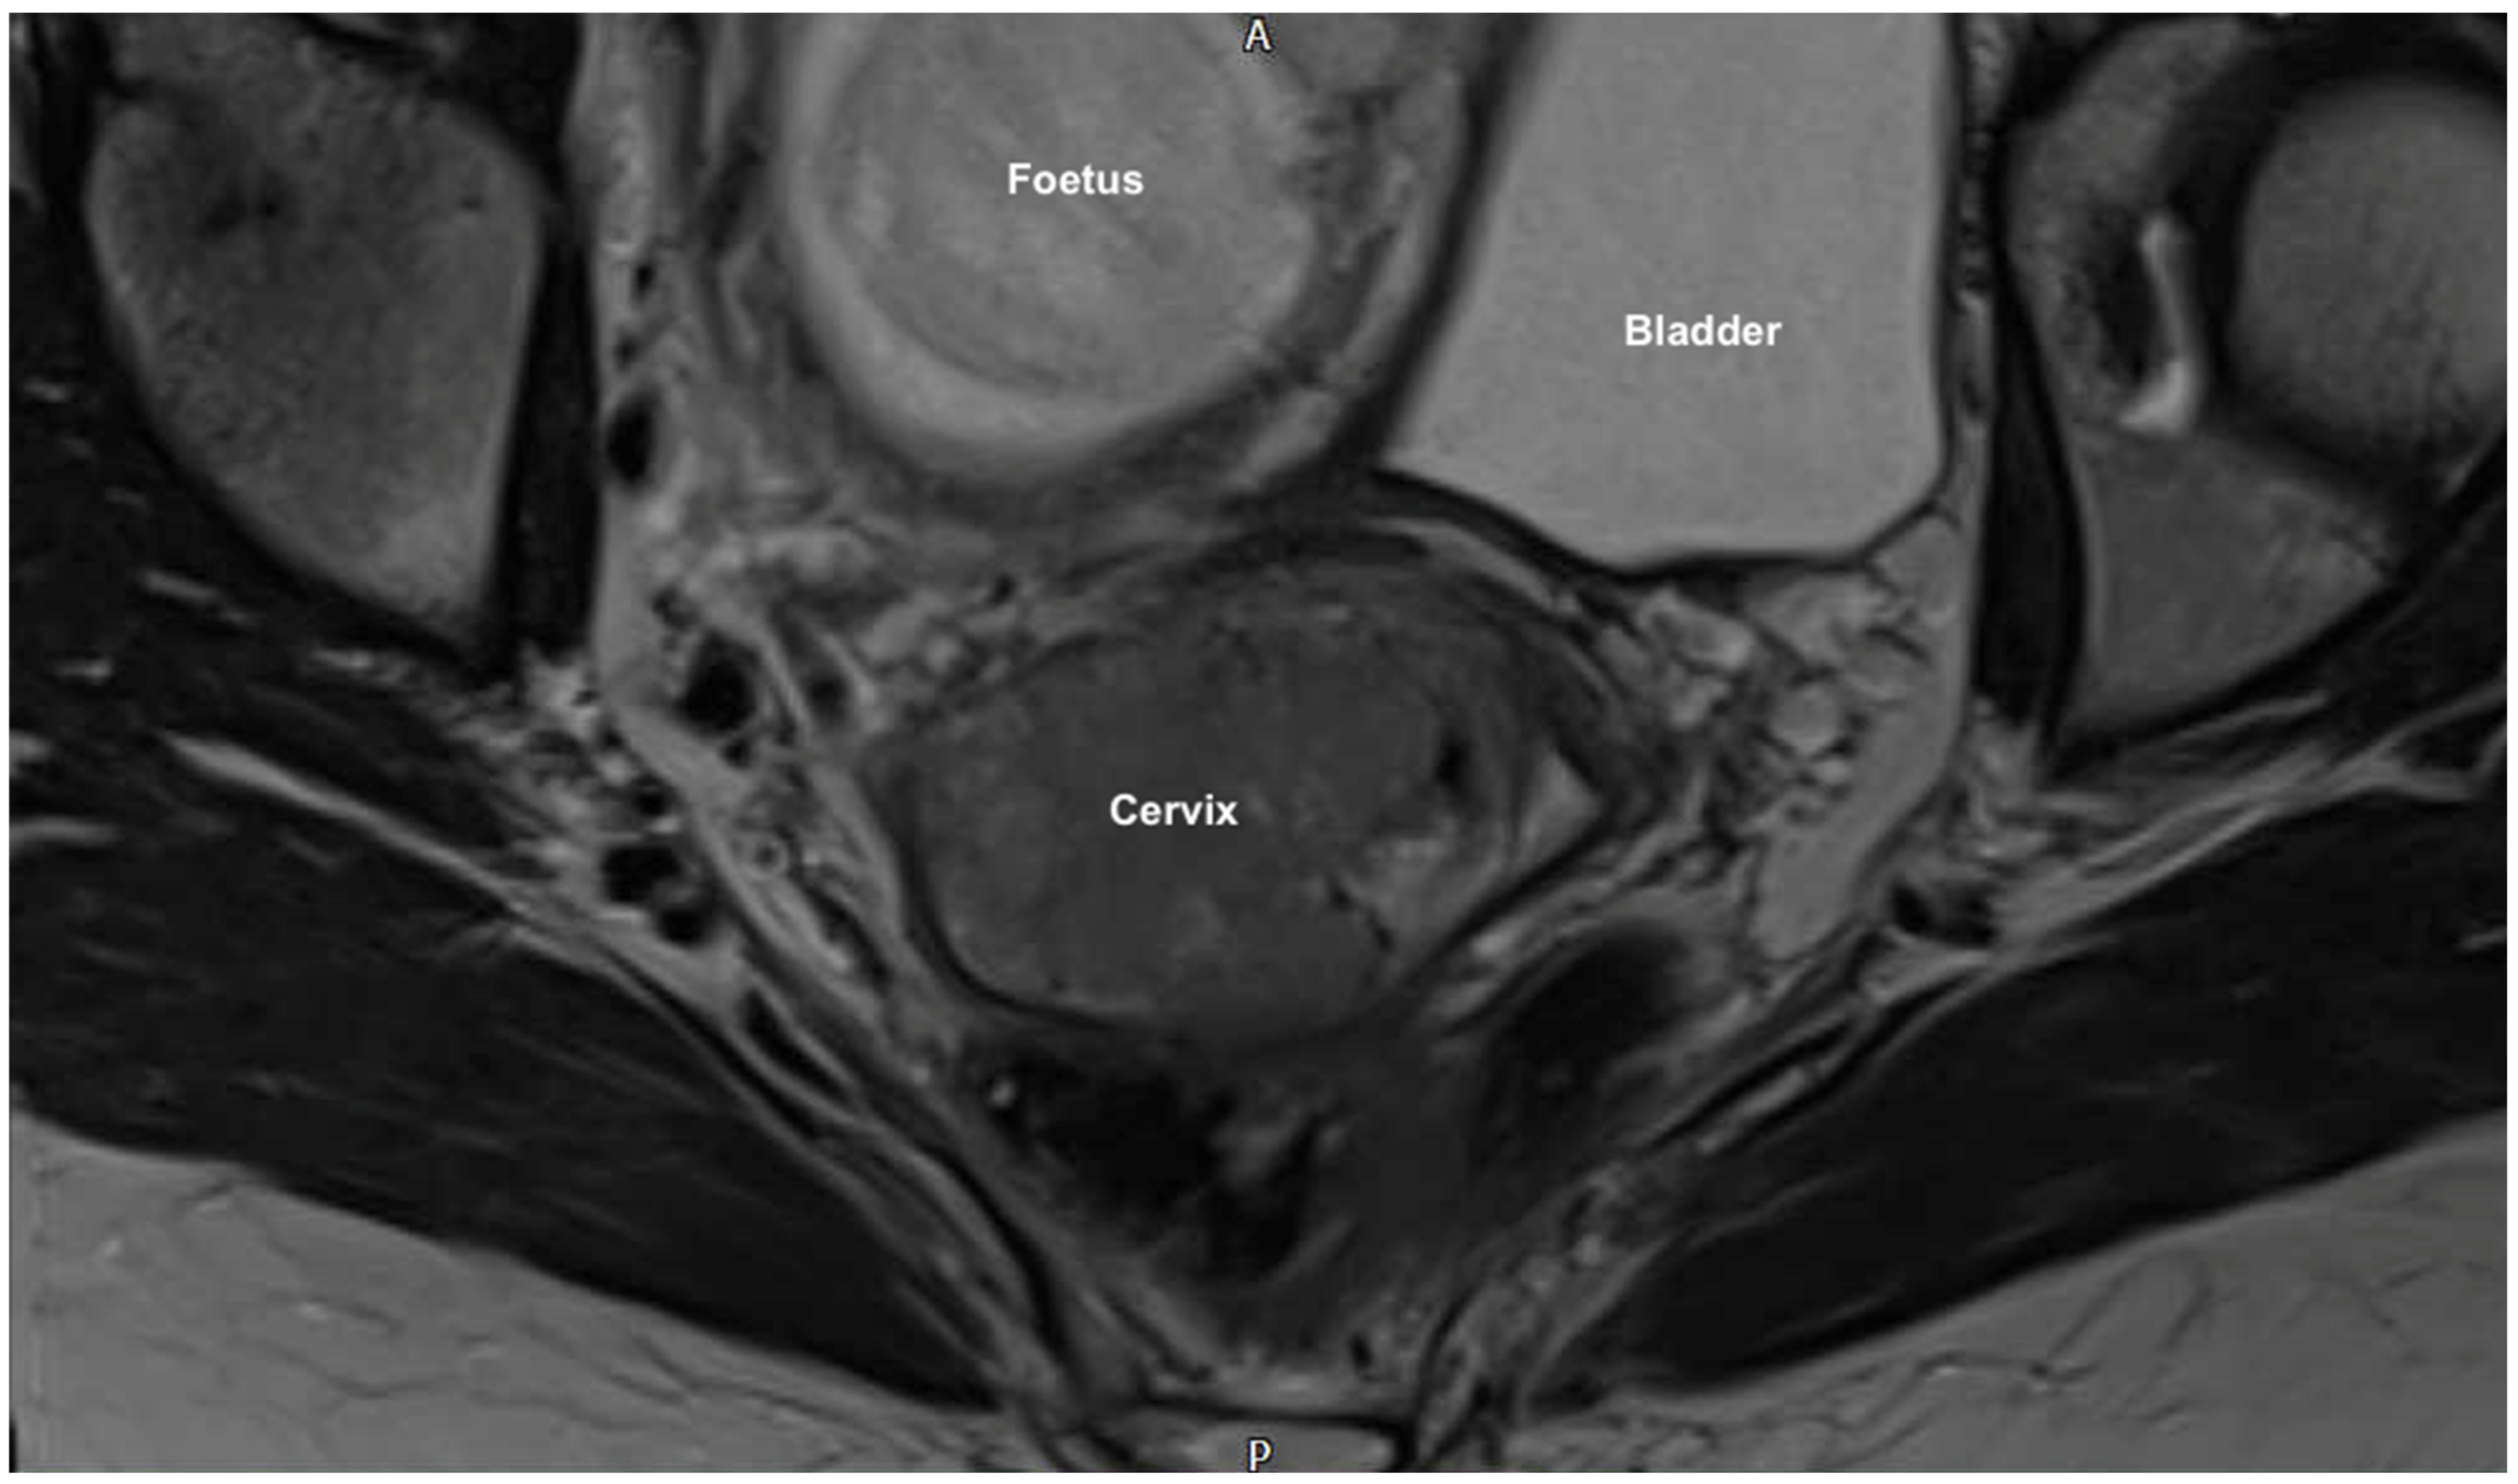

- Findings were of an exophytic 5 cm tumour, which had completely replaced the ectocervix and an 18-week gestation gravid uterus. Pelvic and abdominal structures were otherwise normal in appearance.